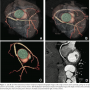

A CTCA was performed (Figure 1, Video 1). There was a single coronary artery, which arose from the right coronary sinus and bifurcated into the RCA and left main (LM) coronary artery. The RCA followed its expected course in the right AV groove. The LM coronary artery passed between the aorta and pulmonary trunk in an unfavorable configuration. At the anterior interventricular groove, the anomalous LM gave rise to the LAD and then continued to supply the LCx artery. There was an arterial conduit connecting the posterolateral RCA and LCx, which completed a ring that traversed the entire AV groove.

A congenital, abnormal communicating artery between the RCA and LCx arteries has previously been reported.7 However, to our knowledge, this is the first report of both coronary anomalies occurring in the same patient. We propose the name Ella’s Locket for this anomaly. We posit that the arterial collateral creating a coronary ring may protect against ischemia from the unfavorable, interarterial anatomy of the LM coronary artery.

Non-invasive imaging techniques including CTCA and magnetic resonance imaging can be useful in understanding coronary anomalies by allowing accurate visualization of coronary anatomy as well as their relationship to adjacent cardiac structures.8-10 Furthermore, the availability of multiple views including 3-dimensional reconstructions can aid diagnostic interpretation.9,10 In addition, the CTCA allows accurate coronary assessment while avoiding potential morbidity associated with invasive coronary imaging.